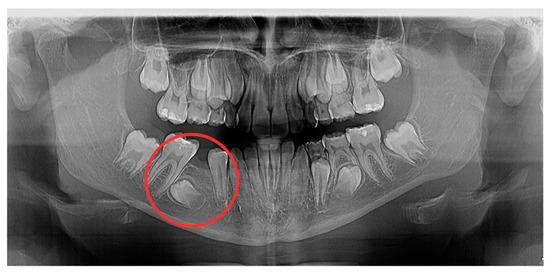

2.1. Examination, Diagnostics, and Initial Therapeutic Management